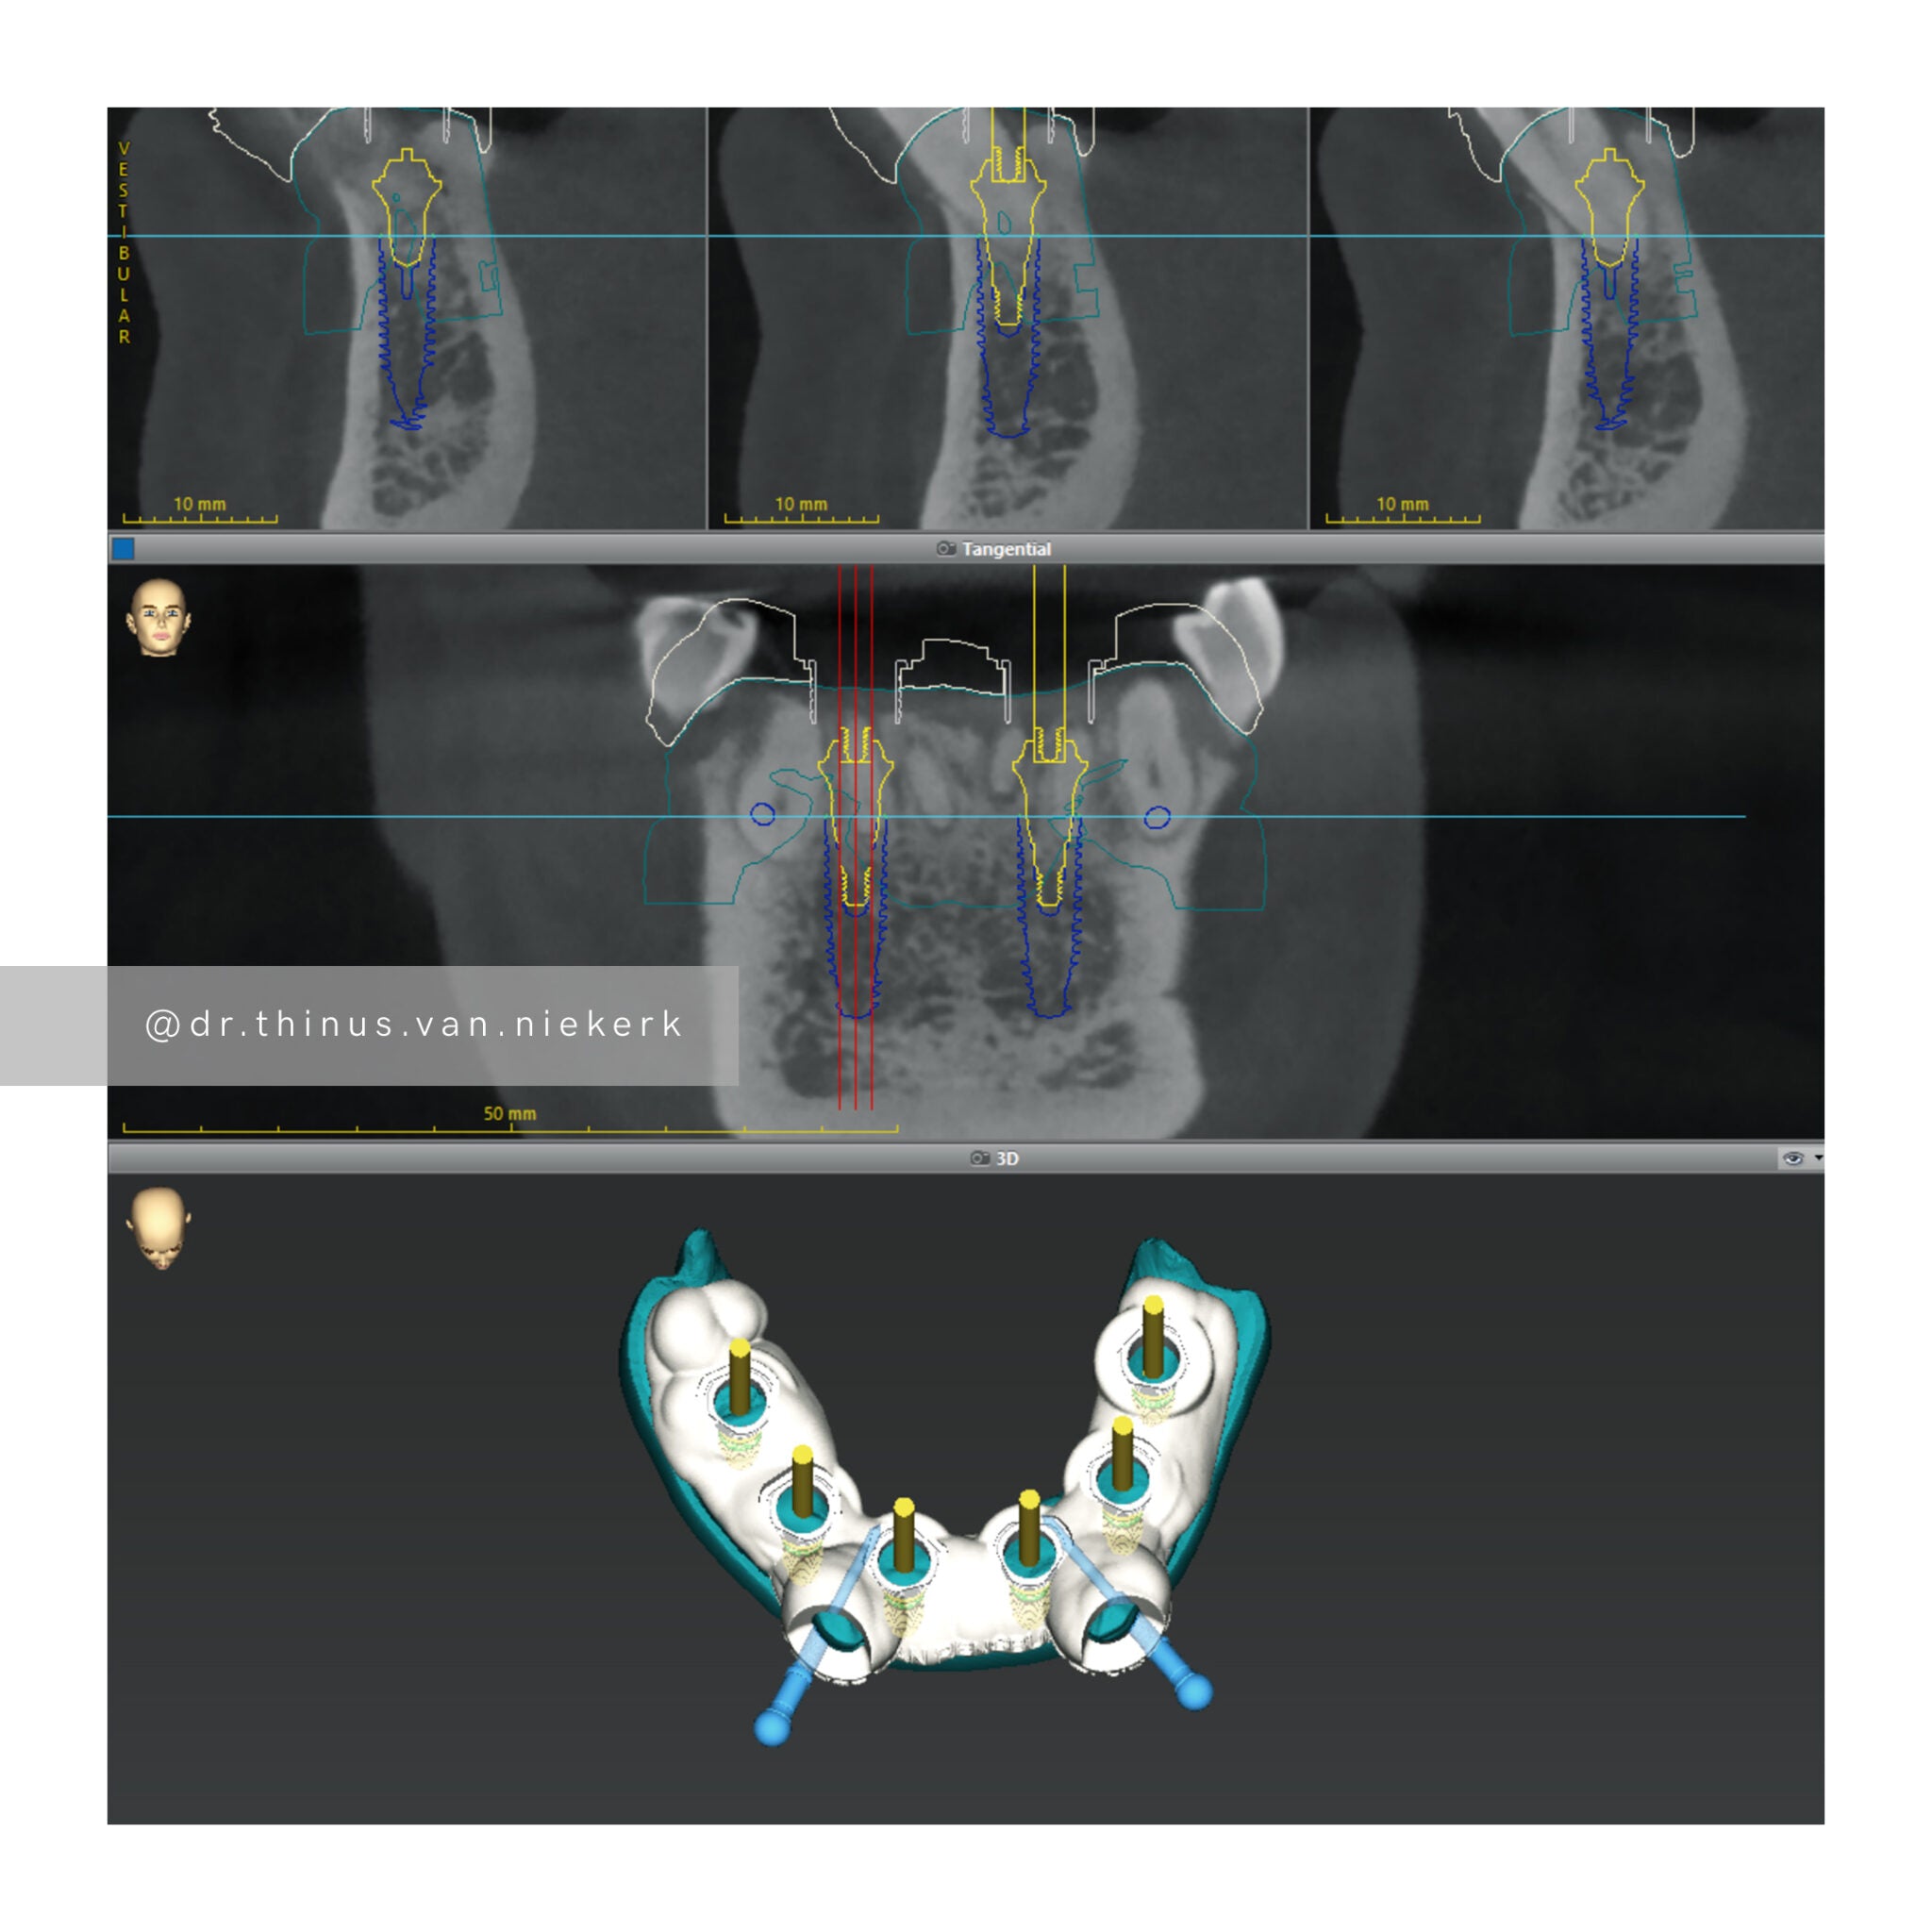

TREATMENT OBJECTIVE

Our aim was to remove all elements of infection and disease and to restore function as quickly as possible. The complete case was digitally planned prior to the day of surgery. Six fully-guided implants were placed during a two-hour morning surgery. An immediate implant-supported prosthesis was delivered on the same day.

COMMENTS

This case demonstrated the power and effectiveness of digital implant-surgery planning and CAD design software.